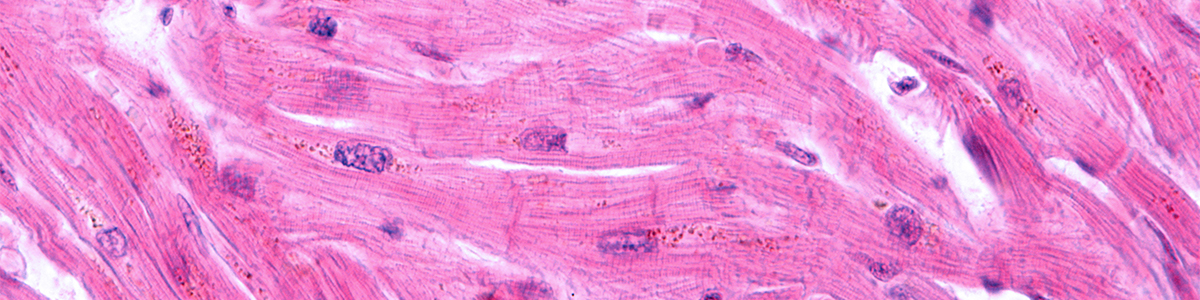

Striated cardiac myocytes cell

Ischemic heart disease remains the leading cause of death in Canada and worldwide. Modern medical management has improved the prognosis of patients after a myocardial infarction (MI), commonly known as a heart attack, but existing therapies are largely aimed at slowing disease progression rather than restoring lost contractile function. Transplantation of cardiomyocytes (heart muscle cells) produced from human pluripotent stem cells (hPSCs) offers a potential new therapy that could, for the first time, remuscularize and repair the heart.

Drs. Gordon Keller and Michael Laflamme's laboratories are collaborating on the development of novel therapies for post-MI heart failure based on the transplantation of cardiomyocytes into the damaged area of the heart. Our goal is to restore the electrical and contractile function of injured hearts by generating new muscle in the scarred (damaged) area with hPSC-derived cardiomyocytes.

Their laboratories have already made a number of important advances in this area, including the development of efficient protocols to guide hPSCs to generate specialized cardiac subtypes, proof-of-concept transplantation studies with hPSC-derived cardiomyocytes in rodent MI models, and the first direct demonstration that hPSC-derived cardiomyocytes can become electrically integrated and beat synchronously with the host heart tissue. Our ongoing work builds on these successes to advance the development of a viable cell therapy for heart disease.